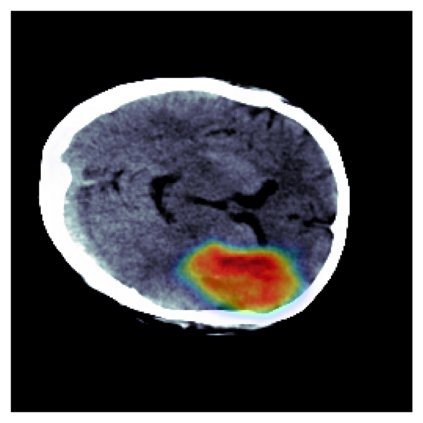

The sigmoid activation is the standard output activation function in binary classification and segmentation with neural networks. Still, there exist a variety of other potential output activation functions, which may lead to improved results in medical image segmentation. In this work, we consider how the asymptotic behavior of different output activation and loss functions affects the prediction probabilities and the corresponding segmentation errors. For cross entropy, we show that a faster rate of change of the activation function correlates with better predictions, while a slower rate of change can improve the calibration of probabilities. For dice loss, we found that the arctangent activation function is superior to the sigmoid function. Furthermore, we provide a test space for arbitrary output activation functions in the area of medical image segmentation. We tested seven activation functions in combination with three loss functions on four different medical image segmentation tasks to provide a classification of which function is best suited in this application scenario.